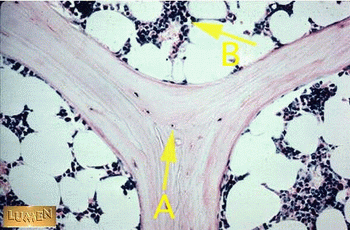

그림 9. 골수 생검조직의 저배율 사진

A: Bone marrow, B: Bone matrix, C: Skeletal muscle,  A: Osteocyte B: Hemopoietic cells